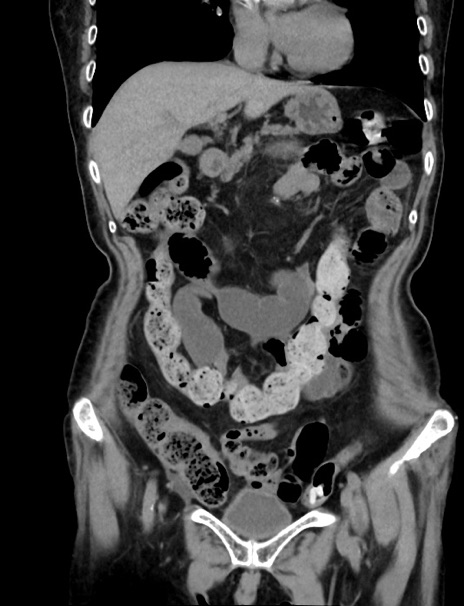

症例33(冠状断像)

【症例】70歳代 女性

【主訴】心窩部痛

【現病歴】延髄病変の精査・加療にて神経内科入院中。本日より心窩部痛あり。

【既往歴】虫垂炎

【身体所見】右下腹部を中心に圧痛と反跳痛あり。

【データ】WBC 10900、CRP 0.02